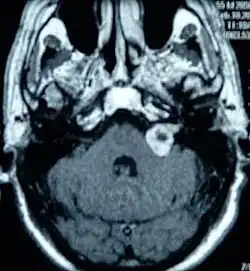

Schwannoma nerwu przedsionkowo-ślimakowego (ang. acoustic neuroma, vestibular schwannoma) – pierwotny, niezłośliwy histologicznie nowotwór części przedsionkowej nerwu przedsionkowo-ślimakowego (VIII), wywodzący się z komórek osłonki nerwowej (komórek Schwanna).

Schwannoma nerwu przedsionkowo-ślimakowego wywodzi się z części przedsionkowej nerwu VIII, równie często z obu jej gałęzi. Najczęstszym miejscem wyjścia guza jest strefa przejścia między tkanką glejową a osłonką Schwanna nerwu, tzw. strefa Obersteinera-Redlicha.